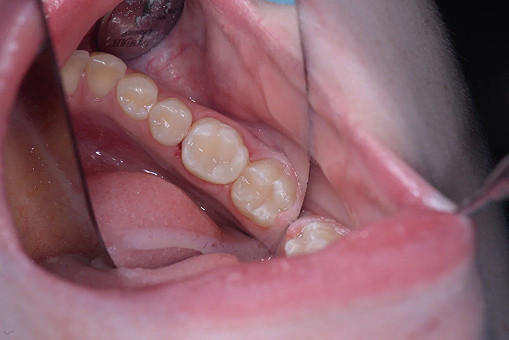

Лечение кариеса проводится следующим образом - сбор анамнеза, проведение местной анестезии, дентальный снимок (при необходимости), изоляция (коффердам), фотопротокол, удаление кариозных тканей (с использованием бора), антисептическая обработка полости, реставрация пломбировочным материалом, шлифовка, полировка.

До/после лечения